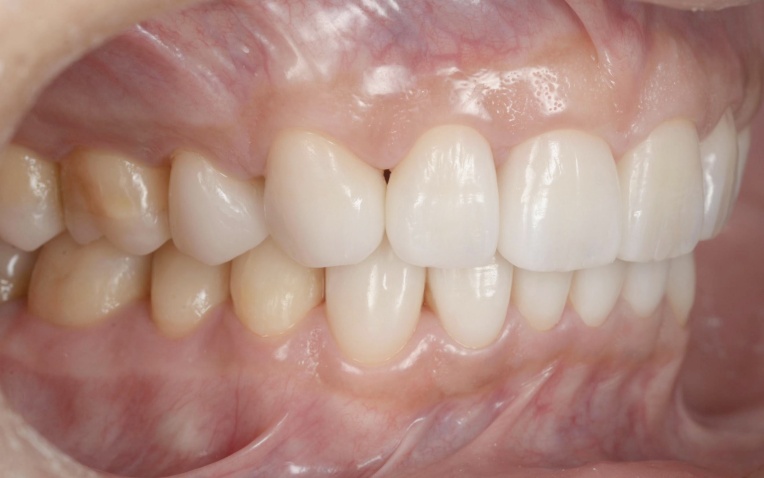

治療後

顎の位置が改善し、噛み合わせが安定したことを確認したあと、装着していた仮歯を除去してセラミックの被せ物に置き換えました。

最後に噛み合わせや見た目に問題がないかをしっかりとチェックして、治療を終了しています。